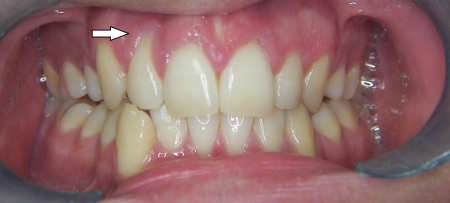

Kompresija –fiksni aparat i ekstrakcija jednog donjeg sjekutića

U sljedećem primjeru prikazan je pacijent s kompresijom koji je već bio u ortodontskoj terapiji. Za rješavanje kompresije donje čeljusti izvađen je sjekutić. Nkon terapije je došlo i do smanjenja recesija na očnjacima jer smo pomakli zubni korijen u bolji položaj.